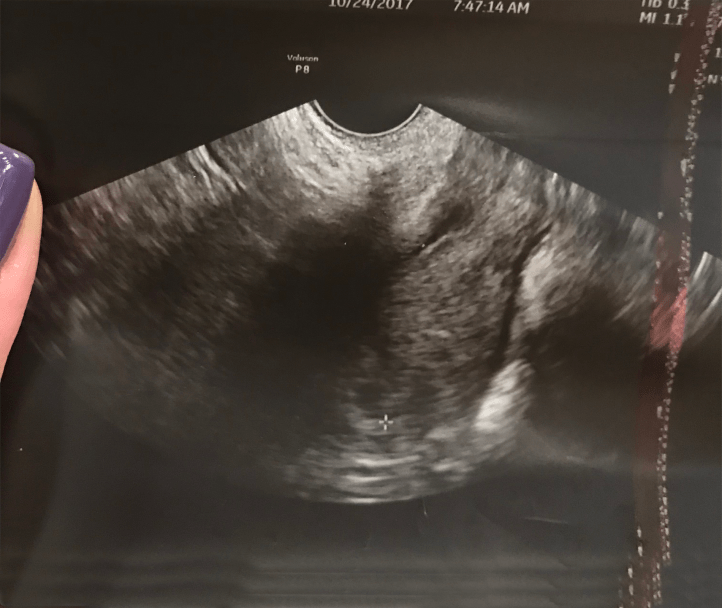

On October 24th, we went for our first ultrasound to see our baby girl. This was the most beautiful black circle we had ever seen!

5 Weeks pregnant.